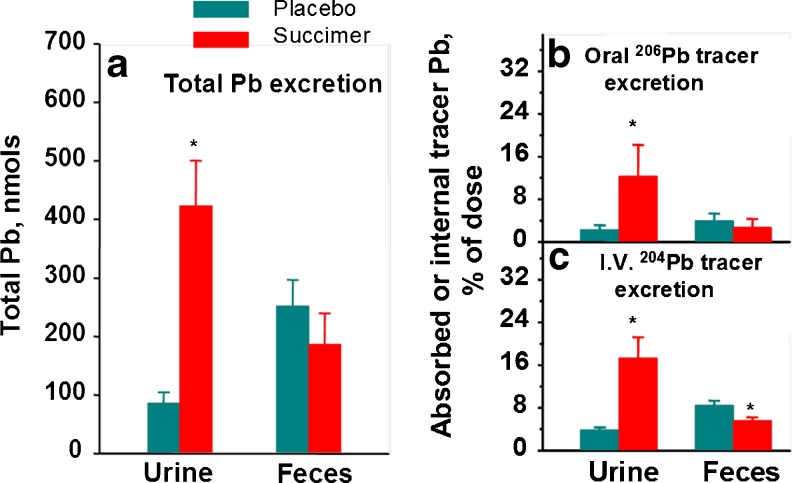

We also evaluated fecal lead elimination with chelation, using complete 24-h fecal samples collected over the first 5 days of treatment [12]. These data are summarized in Fig. 6 along with the urinary lead elimination data. Together these data show that the vast majority of body lead elimination with succimer chelation occurs via urine, with comparatively little eliminated via the fecal route. As noted earlier, we also administered several different stable lead isotope tracers to these monkeys prior to starting chelation, with stable 204Pb tracer administered via i.v. injection and stable 206Pb tracer administered orally. Use of these isotope tracers allowed us to more accurately evaluate elimination of endogenous lead via urinary versus fecal routes, as well as the GI absorption and subsequent elimination of lead present in the GI tract during chelation. Results from these studies substantiate the predominance of urinary lead elimination with succimer treatment, with urinary lead elimination increasing for both the i.v. administered lead tracer (204Pb) and the orally administered tracer (206Pb)—the latter reflecting elimination of oral 206Pb tracer absorbed into the body and subsequently eliminated. Notably, however, the i.v. 204Pb tracer data revealed that the increase in urinary lead elimination with succimer treatment came somewhat at the expense of a decrease in fecal lead elimination, evidenced by a significant reduction in fecal lead elimination with succimer treatment compared to placebo-vehicle (Fig. 6c).

Fig. 6.

Left panel a—effect of oral succimer on urinary and fecal excretion of total lead (inherent lead + stable lead isotope tracers). Right panel b—total urinary and fecal excretion of orally administered 206Pb tracer over the first 5 days of succimer treatment; right panel c—total urinary and fecal excretion of i.v. administered 204Pb tracer over the first 5 days of treatment. Bars are mean ± SE for the vehicle (n = 7) and succimer (n = 8–9) groups. *Significantly different from placebo-vehicle control (p < 0.05). Data from Cremin et al. [12]. [Reproduced with permission from Environmental Health Perspectives]

With the stable lead isotope tracer approach we were also able to evaluate the whole body elimination vs. retention of lead with chelation by assessing the total amount of orally administered 206Pb and i.v. administered 204Pb tracer that was recovered over the first 5 days of succimer treatment. Interestingly, both with orally and i.v. administered lead the amount of tracer recovered in feces and urine was proportionally small relative to the amount of the administered tracer dose (Fig. 7). The fact that animals retained a substantial amount of the administered lead tracers versus what was eliminated with succimer treatment over the 5-day period was surprising.

Fig. 7.

Effects of oral succimer on the retention of orally administered lead absorbed across the gastrointestinal tract (oral 206Pb tracer) and i.v. administered lead (i.v. 204Pb tracer) expressed as a percentage of the administered (204Pb tracer) or calculated (206Pb tracer) internal dose. The internal dose is the amount of the endogenous 204Pb tracer injected i.v. or the amount of the oral 206Pb tracer absorbed from the GI tract. The sum of the lead tracer retained over the first 5 days of succimer treatment is expressed as a percentage of the internal dose, which equals the amount of oral 206Pb tracer absorbed or the amount of 204Pb tracer that was injected. The bars represent mean ± SE for the vehicle (n = 7) and succimer (n = 9) groups. *Succimer group differs from the vehicle group according to an ANOVA (p < 0.05). Data from Cremin et al. [12]. [Reproduced with permission from Environmental Health Perspectives]

Overall, these data show that succimer treatment certainly facilitates the elimination of lead from the body, primarily via a urinary pathway. However, the substantial amounts of orally or i.v. administered lead tracer that were retained in the body in both vehicle- and succimer-treated groups after 5 days of treatment indicates that the vast majority of body lead from recent exposures is not affected by succimer chelation.